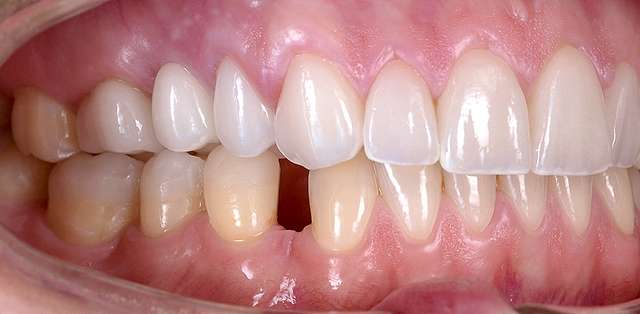

A mock-up is the visual side of a treatment plan. Consider the treatment plan as something scriptic, that contains price estimates and procedures, some hard to understand. Consider the treatment plan as the text , whereas the mock-up is the drawing meant to explain it. Traditionally the mock-up was used to test prosthetic design of a future restoration. In present times the mock-up is used at the beginning of most rehabilitations to express visually the esthetic impact of the proposed treatment plan. The entire process is non invasive and reversible. The mock-up is transferred on top of the existing teeth, whenever possible , and a series of optical ilusions is used in order to simulate the future smile. Generally it is communicated to the patient via pictures or videos, that will serve as the draft for communication between patient and the team treating him.

The mock-up just like a treatment plan can simulate a diverse array of procedures that vary on cases basis. In this case, we have dental implants and tissue grafts in posterior areas, on both sides, and ceramic veneers and crown lengthening in anterior side to balance the smile. As a fine detail , you can see how the dentist uses a black marker to simulate the area of the tooth which will be reduced. The mock-up, once accepted becomes a cental pillar in an interdisciplinary treatment. It will be used to determine how the gums will be remodelled , where the implants should be placed, and how the teeth need to be prepped for the future restorations.